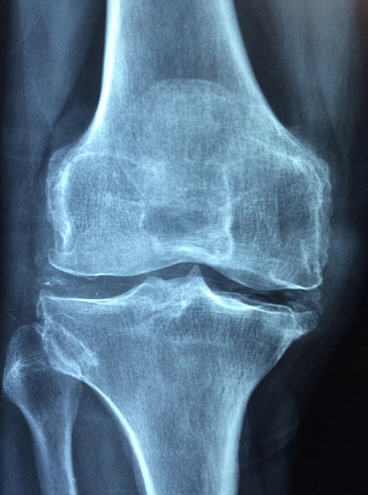

| X-ray(엑스레이) | 뼈 모양·관절 간격 확인 |

| MRI | 연골·인대·연부조직 손상 확인 |